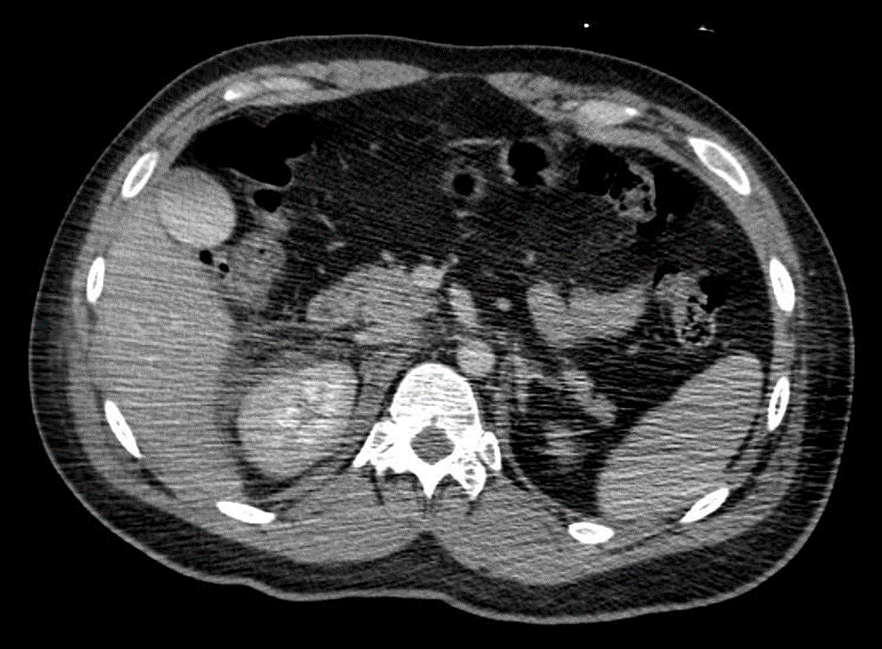

TC abdome e pelve com contraste endovenoso (EV) (02/04/2025): Derrame pleural bilateral – Hemoperitônio disperso na cavidade. Aumento e borramento da adrenal direita, inferindo contusão / laceração. Fígado, pâncreas e adrenal esquerda com situação, dimensões, contornos e coeficientes de atenuação normais. Baço homogêneo. Linha tênue no contorno superior do baço de difícil caracterização devido a artefatos. Ausência de sinais de dilatação das vias biliares intra ou extra-hepáticas. Vesícula biliar normodistendida, paredes finas e conteúdo homogêneo. Rins com topografia, morfologia, dimensões, eixo, contornos e espessura do parênquima normais, não se observando sinais de dilatação dos sistemas coletores. Boa concentração e eliminação do meio de contraste, bilateralmente. Aorta e veia cava inferior com calibre e contornos normais. Ausência de linfonodomegalias retroperitoneais e pélvica. Bexiga repleta, apresentando contornos regulares e conteúdo homogêneo. Próstata com contornos regulares e densidade tomográfica preservada. Trato gastrointestinal de aspecto habitual. Hérnia umbilical, com conteúdo lipomatoso. Fratura cominutiva do colo femoral direito, com desvio.

Figura 5: Tomografia Computadorizada de abdome.

Figura 6: Tomografia Computadorizada de abdome.

TC abdome e pelve com contraste EV (03/04/25): Derrame pleural bilateral, determinando atelectasia passiva. Hematoma adrenal direita medindo 3 cm. Moderado hemoperitônio. Pequeno borramento da gordura perirrenal direita. Fratura em colo femoral direito com desvio. Sem demais alterações agudas do trauma.

Figura 7: Tomografia Computadorizada de abdome.